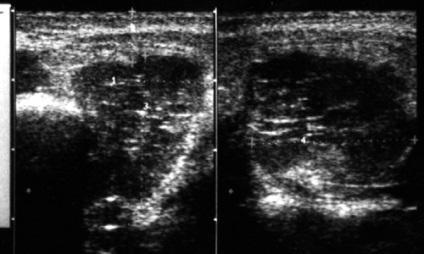

Nagyon fontos szerepe van ultrahang érzékelésére daganatok a nyálmirigyek. Képesség részletes értékelése áramkörök neoplazmák és annak belső szerkezete (ehostruktury) lehetővé teszi a nagy megbízhatóság megkülönböztetni jóindulatú daganatok a rosszindulatú nyálmirigy daganatok (ábra. 34-36).

Ábra. 34. A polimorf adenoma a bal parotisban.

Ábra. 35. Lipoma bal parotisban.

Ábra. 36. rosszindulatú daganata a jobb fültőmirigy (szövettan: differenciálatlan karcinóma).